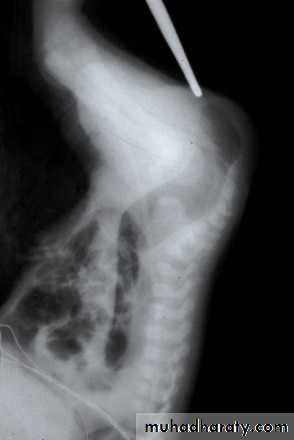

(Invertogram) or (prone cross table lateral film): after 24 hr from birth , the baby is held upside down(invertogram) or placed in prone genu-pectroral position for 3 min., then lateral view X-ray is taken centered on greater trochanter & P-C line (pubis-coccyx) with marker applied at the natal cleft on the site of anal dimple. If the gas shadow in rectum is proximal to P-C line = high type imperforate anus & need initial colostomy while if the gas shadow in rectum is distal to P-C line = low type imperforate anus & no need for colostomy, just perineal anoplasty. Or we measure the bowel – skin distance, if more than 2 cm = high type need colostomy, if less than 2 cm = low type , no colostomy is needed just perineal anoplasty.

Low type high type meconium per urethra